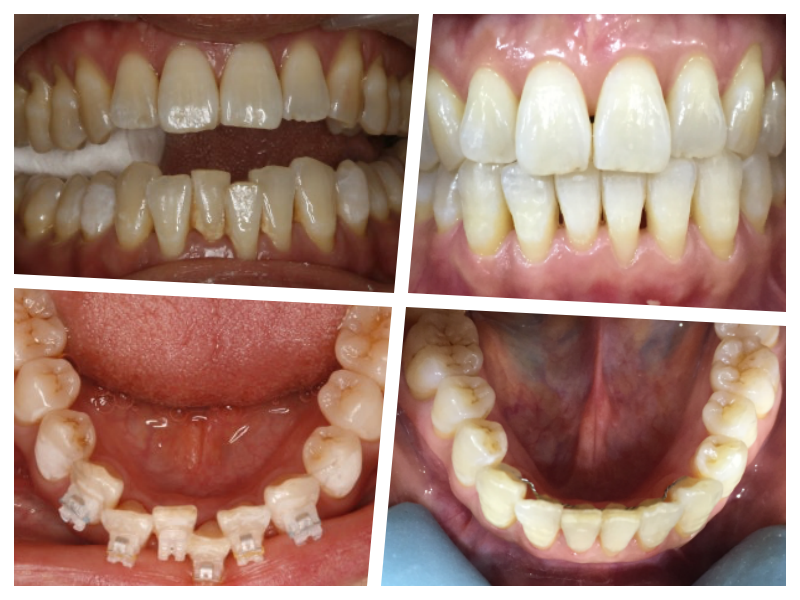

치아 교정

3D 스캔 투명교정으로 간편한 교정치료를 제공합니다.

치아 교정 치료는 기능성과 심미성이 적절한 조화가 이루어져야만 성공적인 치아 교정이라 할 수 있습니다.그렇기에 실력있는 의료진이 축적된 노하우와 기술로 부작용을 최소화하여 환자가 원하는 이상적인 치료 결과를 만들어 내야 합니다. 개인마다 식습관, 치아의 배열, 얼굴의 형태, 라이프스타일 등 전부 다 각기 다르므로 이 모든 항목들을 꼼꼼하게 체크한 후 개개인에게 맞는 맞춤 진단이 필요합니다.